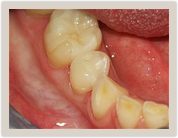

| Before Photo | After Photo |

Removal of an amalgam (silver) filling and replacement with a natural tooth colored full-ceramic filling using the CEREC system.